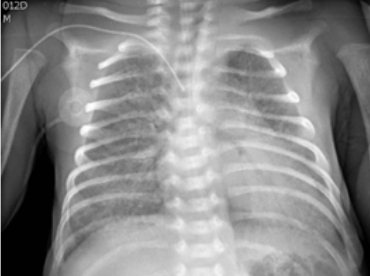

• Rx de torax

. Se ob-serva gran hiperinsuflación, compromiso inters-ticial difuso bilateral y condensación con dismi-nución de volumen y broncograma aéreo de LII (retrocardio)